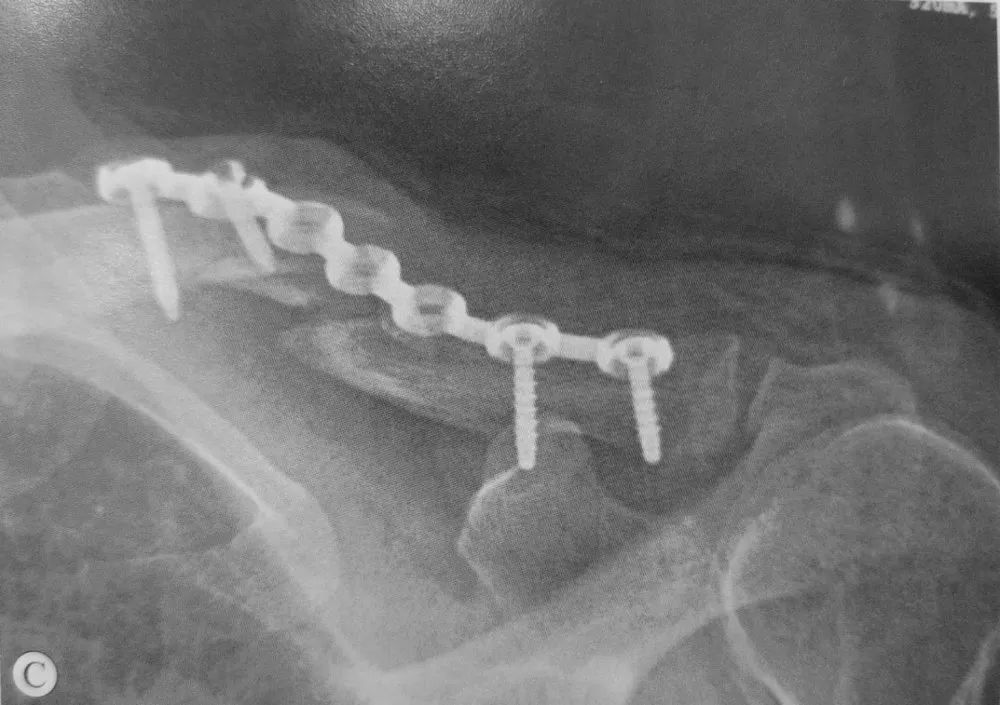

▲ 中1/3锁骨骨折患者,行切开复位内固定术,重建钢板安置于锁骨上表面,术前(A)及术后(B)X线片

▲ 内固定不牢固造成固定及骨折移位

A:锁骨中段骨折;

B:内固定术后即刻X线片;

C:术后2个月复查X线片发现骨折移位;

D:发现固定不牢固后用三角巾固定,术后1年X线片发现骨折愈合;

E:术后2年锁骨CT扫描加重建显示骨折愈合并完全塑形;

F:手术取出内固定术后X线片。

▲ 钢板长度过短、骨膜剥离大、使用钢丝致使锁骨骨折骨不连,最终钢板断裂

A:锁骨中段骨折,有蝶形骨块;

B:锁骨内固定术后X线片;

C:术后8个月,钢板折断、骨不连,肩关节活动过程中诉骨折部位疼痛;

D:手术取出内固定见骨折断端;

E:手术过程中取出的断裂钢板以及钢丝、螺钉;

F:内固定取出见骨折断端异常活动;

G:取髂骨断端植骨、锁钉钢板固定术后;

H:骨折不愈合翻修术后X线片。